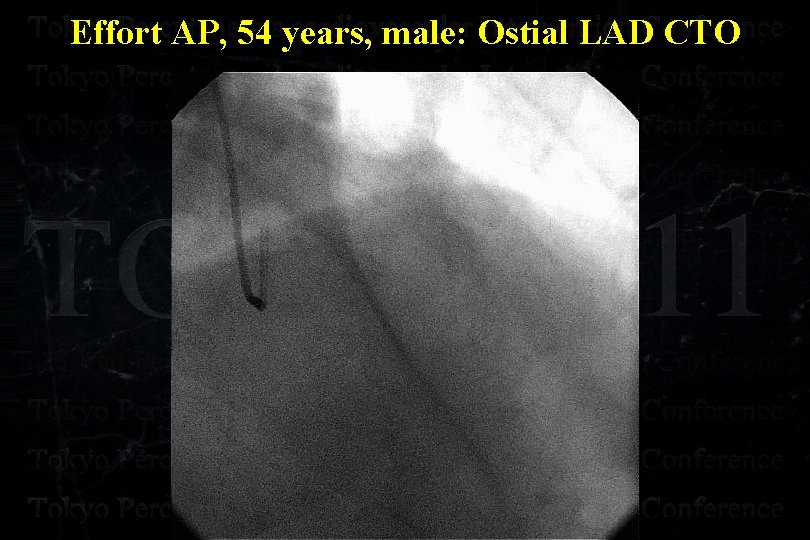

Effort AP, 54 years, male: Ostial LAD CTO

Effort AP, 54 years, male: Ostial LAD CTO

Effort AP, 54 years, male: Ostial LAD CTO

Effort AP, 54 years, male: Ostial LAD CTO

Effort AP, 54 years, male: Ostial LAD CTO

Effort AP, 54 years, male: Ostial LAD CTO 8 Fr Mach 1 FL 4. 0 6 Fr Mach 1 IM